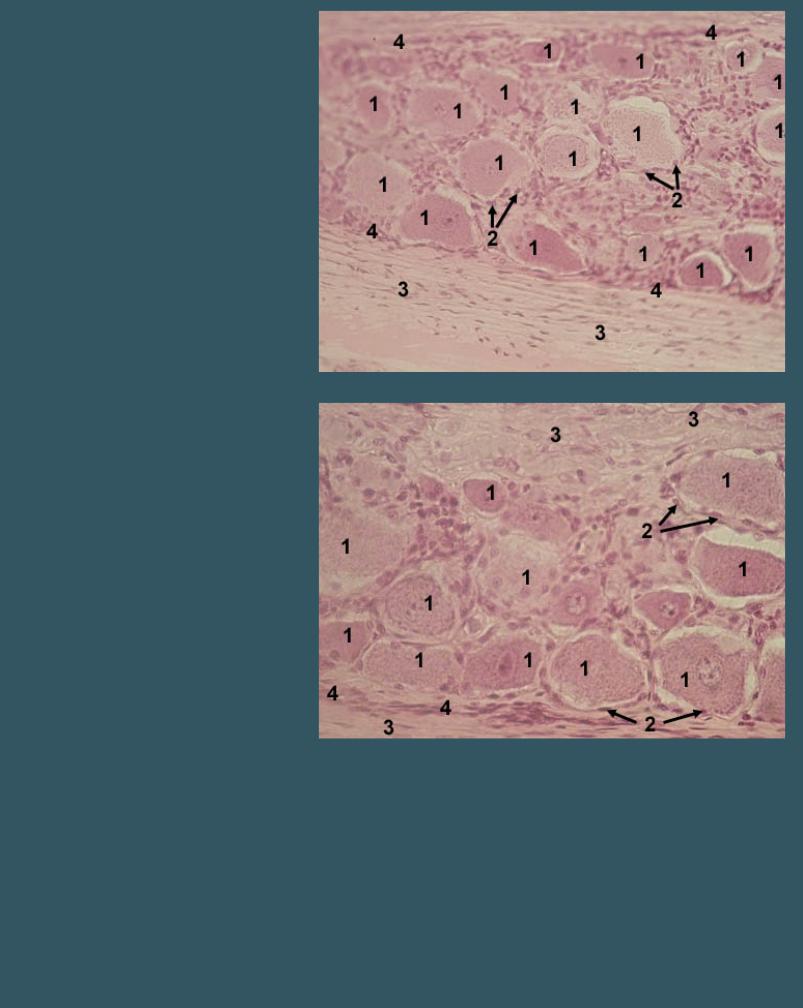

СПИННОМОЗГОВОЙ ГАНГЛИЙ

Окраска гематоксилин-эозином

1 - скопления тел нейронов

2 - нервные волокна

СПИННОМОЗГОВОЙ ГАНГЛИЙ

Окраска гематоксилин-эозином

1 - тела нейронов (псевдоуниполярные нейроны) 2 - нервные волокна

СПИННОМОЗГОВОЙ ГАНГЛИЙ

Окраска гематоксилин-эозином

1 - тела нейронов (псевдоуниполярные нейроны) 2 - клетки-сателлиты 3 - нервные волокна

4 - прослойки соединительной ткани

СПИННОМОЗГОВОЙ ГАНГЛИЙ

Окраска гематоксилин-эозином

1 - тела нейронов (псевдоуниполярные нейроны) 2 - клетки-сателлиты 3 - нервные волокна

4 - прослойки соединительной ткани